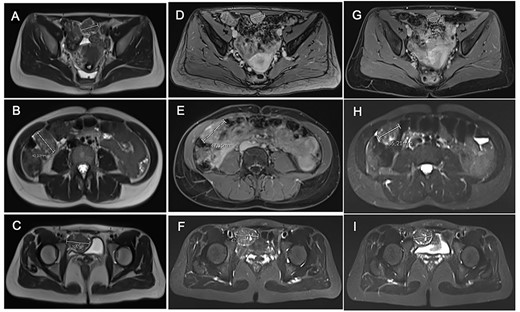

After tumor board discussion, hormonotherapy was recommended. One month after starting Letrozole, the patient expressed her desire for pregnancy and the treatment was switched to ulipristal acetate 5 mg per day. After 3 months of treatment, the abdominal pain persisted without any improvement and MRI re-evaluation showed stability compared with the previous CT (Fig. 3A–C). Given the inefficacy of this treatment, letrozole 5 mg per day was resumed in association with a Gonadotrophin-releasing hormone (GnRH) agonist (Triptorelin 12.5-mg intramuscular 1/month). After 3 months of treatment, MRI revealed a 10% reduction in the size of the three nodules (Fig. 3D–F). Abdominal pain was partially improved and localized in the right hypochondrium. The tumor board proposed MRI reevaluation after 6 months of effective treatment and surgical excision if the symptoms persisted.

Comparative magnetic resonance imaging (MRI). (A–C) MRI after 3 months of acetate ulipristal. (A) Tumor in contact with infra-umbilical linea alba; (B) lesion located in right hypochondria; (C) tumor situated in right iliac fossa near bladder. (D–F) MRI after 3 months of AI and GnRH agonist. (G–I) preoperative MRI.

Treatment was pursued for another 3-month cycle with persistent abdominal discomfort. Control MRI showed the persistent benefit and stability of the three lesions (Fig. 3G–I). Laparoscopy was performed after a total of 6 months of AI and GnRH agonist. Inspection of the abdominopelvic cavity revealed three tumors located in the right hypochondrium, the left para-vesical fossa and the median trocar scar infiltrating the abdominal wall. All three lesions were excised (Fig. 4). Definitive histopathological results showed spindle-cell proliferation of smooth muscle cells (Fig. 5). There was no nuclear atypia, necrosis or mitosis, but the proliferation seemed modified with edema and fibrosis, probably due to the treatment. Tumor cells were smooth muscle actin-, desmin- and caldesmone-positive, confirming their smooth muscle nature. They were CD117- and HMB45-. Ki67 was close to 1%.